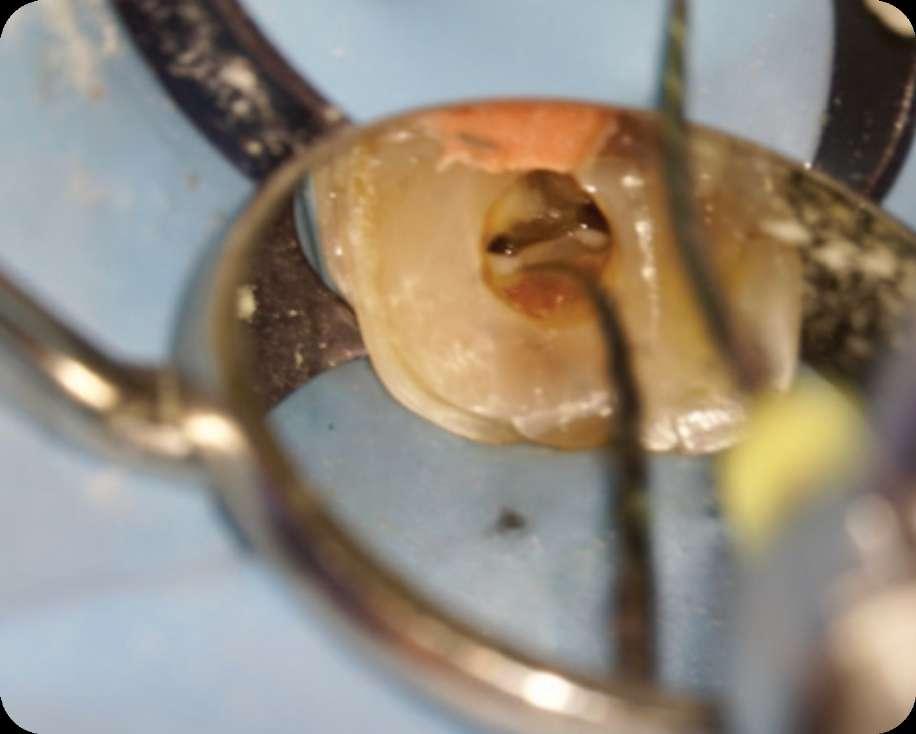

Klinischer Fall

Präoperativ

Der erste untere, linke Backenzahn zeigt einen Zerfall auf dem distalen Teil mit dem Symptom einer irreversiblen Pulpitis. Zuerst wird der Karies entfernt und der Zahn wird mit einer temporären Füllung wieder aufgebaut. Danach wird der Kofferdam platziert und der Zugangshohlraum steht.

Vier Kanäle wurden mit dem SX EdgeTaper Platinum eröffnet. Auch der koronale Teil wurde mit dem S1 EdgeTaper Platinum erweitert. Arbeitslänge und Durchgängigkeit werden mit einer #10 K-Feile erreicht. Die A #15 K-Feile wurde verwendet, um Länge und Durchgängigkeit zu gewährleisten. Dank der Technologie von EdgeNedo war ich im Stande, die Feile für eine komfortable Formgebung vorzuformen, auch wenn die Öffnung reduziert wurde. S1, S2, F1 und F2 EdgeEndo Platin wurde bis zur gesamten Länge des Kanals eingebracht.

Während der Isthmus-Reinigung zeigte sich zwischen den mesialen Kanälen ein zusätzlicher Kanal. Die Formgebungsphase erfolgte schnell und effizient dank SX zum F2.

Das Röntgenbild zeigte eine große Länge und einen gemeinsamen Ausgang für zwei der drei mesialen Kanäle.

Die Wurzelfüllung erfolgte mit einer einzigen Kegeltechnik unter Verwendung des BUSA EndoSequence Bioceramic Sealer. Das Post-OP-Röntgen zeigt sehr hohe Dichte in der gesamten Länge der Wurzelfüllung.